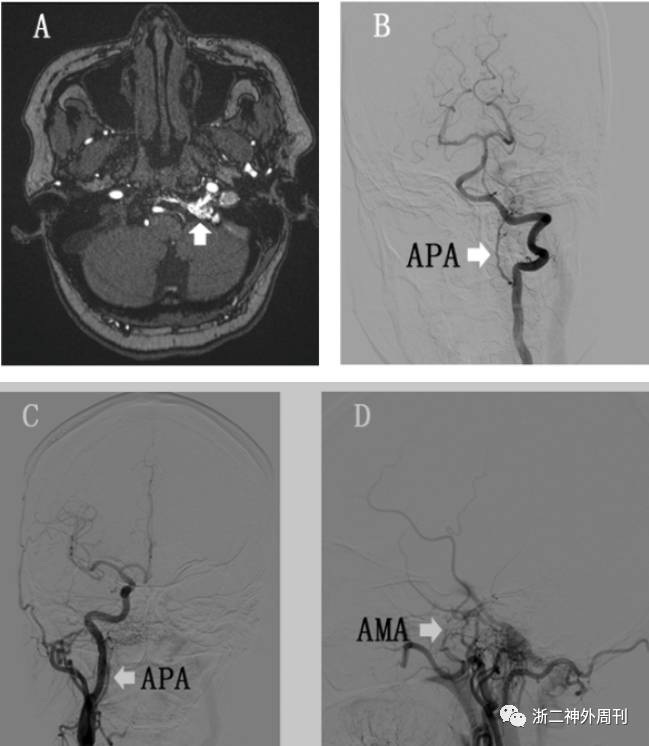

患者于5月前无明显诱因出现左侧耳鸣伴有左侧头痛,无听力下降等,未就诊。1月前症状有所加重,并出现左眼球结膜充血肿胀伴视物模糊,来我院就诊,MRA(3D-TOF )(图1A)检查提示左侧舌下神经管区异常血管。拟诊“硬脑膜动静脉瘘可能”收住入院。

入院后进一步 DSA检查,确诊为舌下神经管区硬脑膜动静脉瘘(hypoglossal canal dural arteriovenous fistulas,HC- DAVF),供血动脉主要为左侧咽升动脉,另外右侧咽升动脉、左侧脑膜前动脉均参与供血。瘘口位于左侧舌下神经管处,静脉引流向上通过岩下窦向海绵窦引流并返流到眼静脉和皮层静脉,向下回流到颈内静脉,并可见有髓周静脉引流(图1B-D)。

图1. A:3D-TOF MRA影显示左侧舌下神经管处异常的紊乱血管(白箭头);B-D:DSA结果提示双侧咽升动脉(APA)及左侧脑膜前动脉(AMA)供血(白色箭头)。